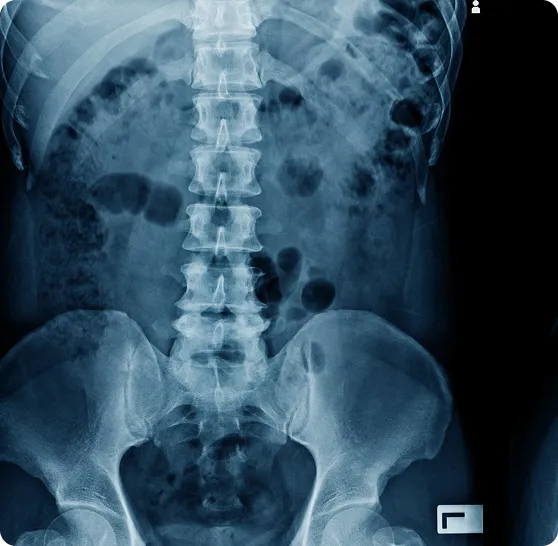

Your body was designed to have a healthy spinal alignment. When viewed from the front, the spine should be straight with level shoulders and hips. From the side, it has gentle curves (neck, mid-back, and low-back) that act as shock absorbers. With proper alignment, each vertebra in the spine moves freely through its full range of motion. This healthy alignment means less wear-and-tear on joints and discs, better flexibility, and maximum protection for the delicate nerves inside the spinal column. Good alignment helps you stand tall, maintain good posture, and allow your nervous system to communicate without interference. In short, a well-aligned spine keeps you mobile and pain-free, and it supports overall wellness from head to toe.

When the Spine is Misaligned (Unhealthy Spine)

An unhealthy or misaligned spine can develop from poor posture, injuries, repetitive strain, or simply the stresses of daily life. When vertebrae shift out of their proper position (a condition chiropractors call a subluxation), it can put abnormal pressure on joints, discs, and nerves. A misaligned spine often leads to abnormal wear and degeneration in the joints and discs over time. It may also cause muscle tension, pain, and even reduced organ function if nerve signals are disrupted. For example, a forward-head posture or loss of the normal neck curve can stretch and irritate the spinal cord and nerves. You might not notice symptoms right away – or you may just feel occasional stiffness or discomfort – but internally, the body is struggling to compensate for the poor alignment. Over time, untreated spinal misalignments can lead to chronic pain, numbness or tingling in the extremities, decreased flexibility, and other health issues. The good news is that chiropractic adjustments can correct these misalignments, restoring proper alignment and nerve flow so your body can heal and function at its best.